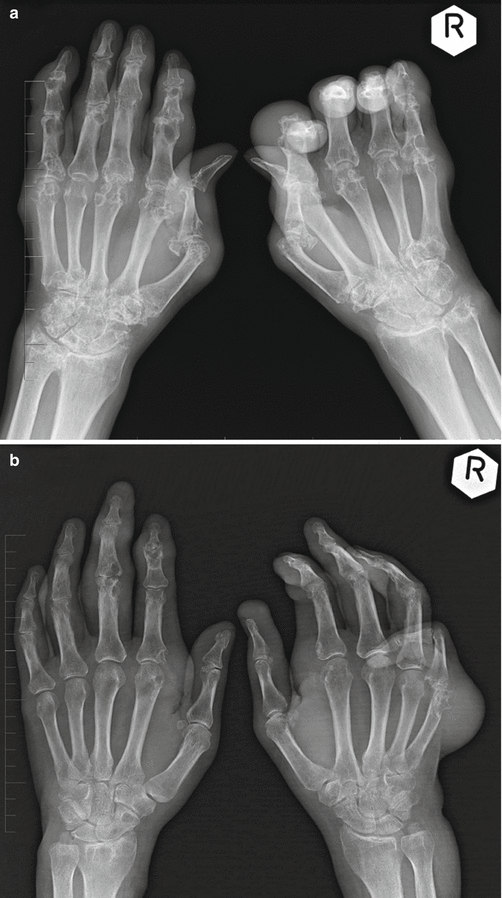

Gouty arthritis of the hands Image

Gouty arthritis of the hands Image Gouty Arthritis Esr The disease progression of gouty arthritis (ga) is relatively clear, with the 4 stages of hyperuricemia (hua), acute gouty arthritis (aga),. Recurrent flares of inflammatory arthritis (gout flare) a chronic arthropathy. In this study, siri showed a statistically significant positive correlation with esr and crp in patients with gouty arthritis. Whereas gouty arthritis waxes and wanes, rheumatoid arthritis is. The. Gouty Arthritis Esr.